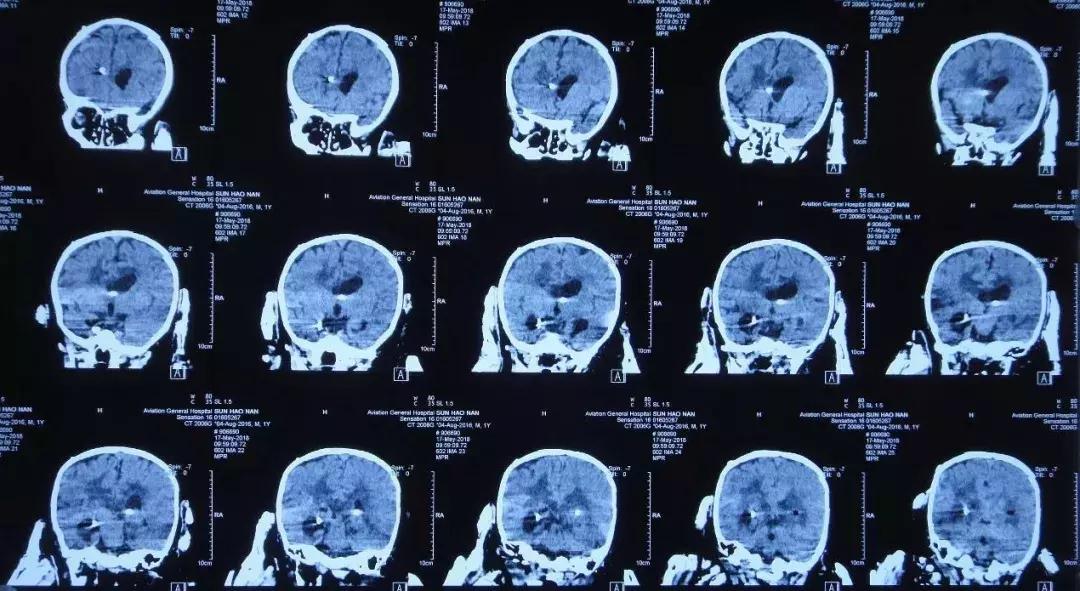

2018年3月26日头部影像检查

2018年3月26日入院当天

初步诊断: 1 中枢神经系统感染,2 脑膜炎,3 脑炎,4 脑室炎,5 脑室粘连,6 继发性脑积水,7 低钠血症,8 营养性贫血,9 脑脓肿。

李小勇主任指导意见:患儿诊断“1、脑积水 2、颅内感染 3、脑室粘连”明确。根据目前情况,需行开颅脑室探查术+透明隔造瘘术+侧脑室腹壁外引流术。疏通脑脊液循环通路,减轻脑组织压迫。

2018年3月27日在全麻醉下行开颅脑室探查术+透明隔造瘘术+双侧侧脑室腹壁外引流术, 术后复查CT:术区未见明显出血。

2018年3月27日术后复查CT